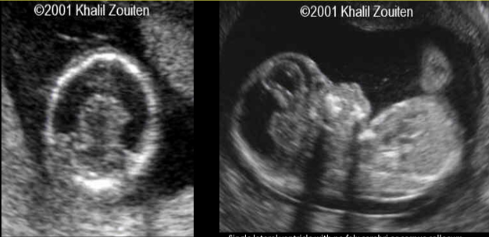

Alobar holoprosencephaly

SINGLE ventricle, fused thalami, absent CC